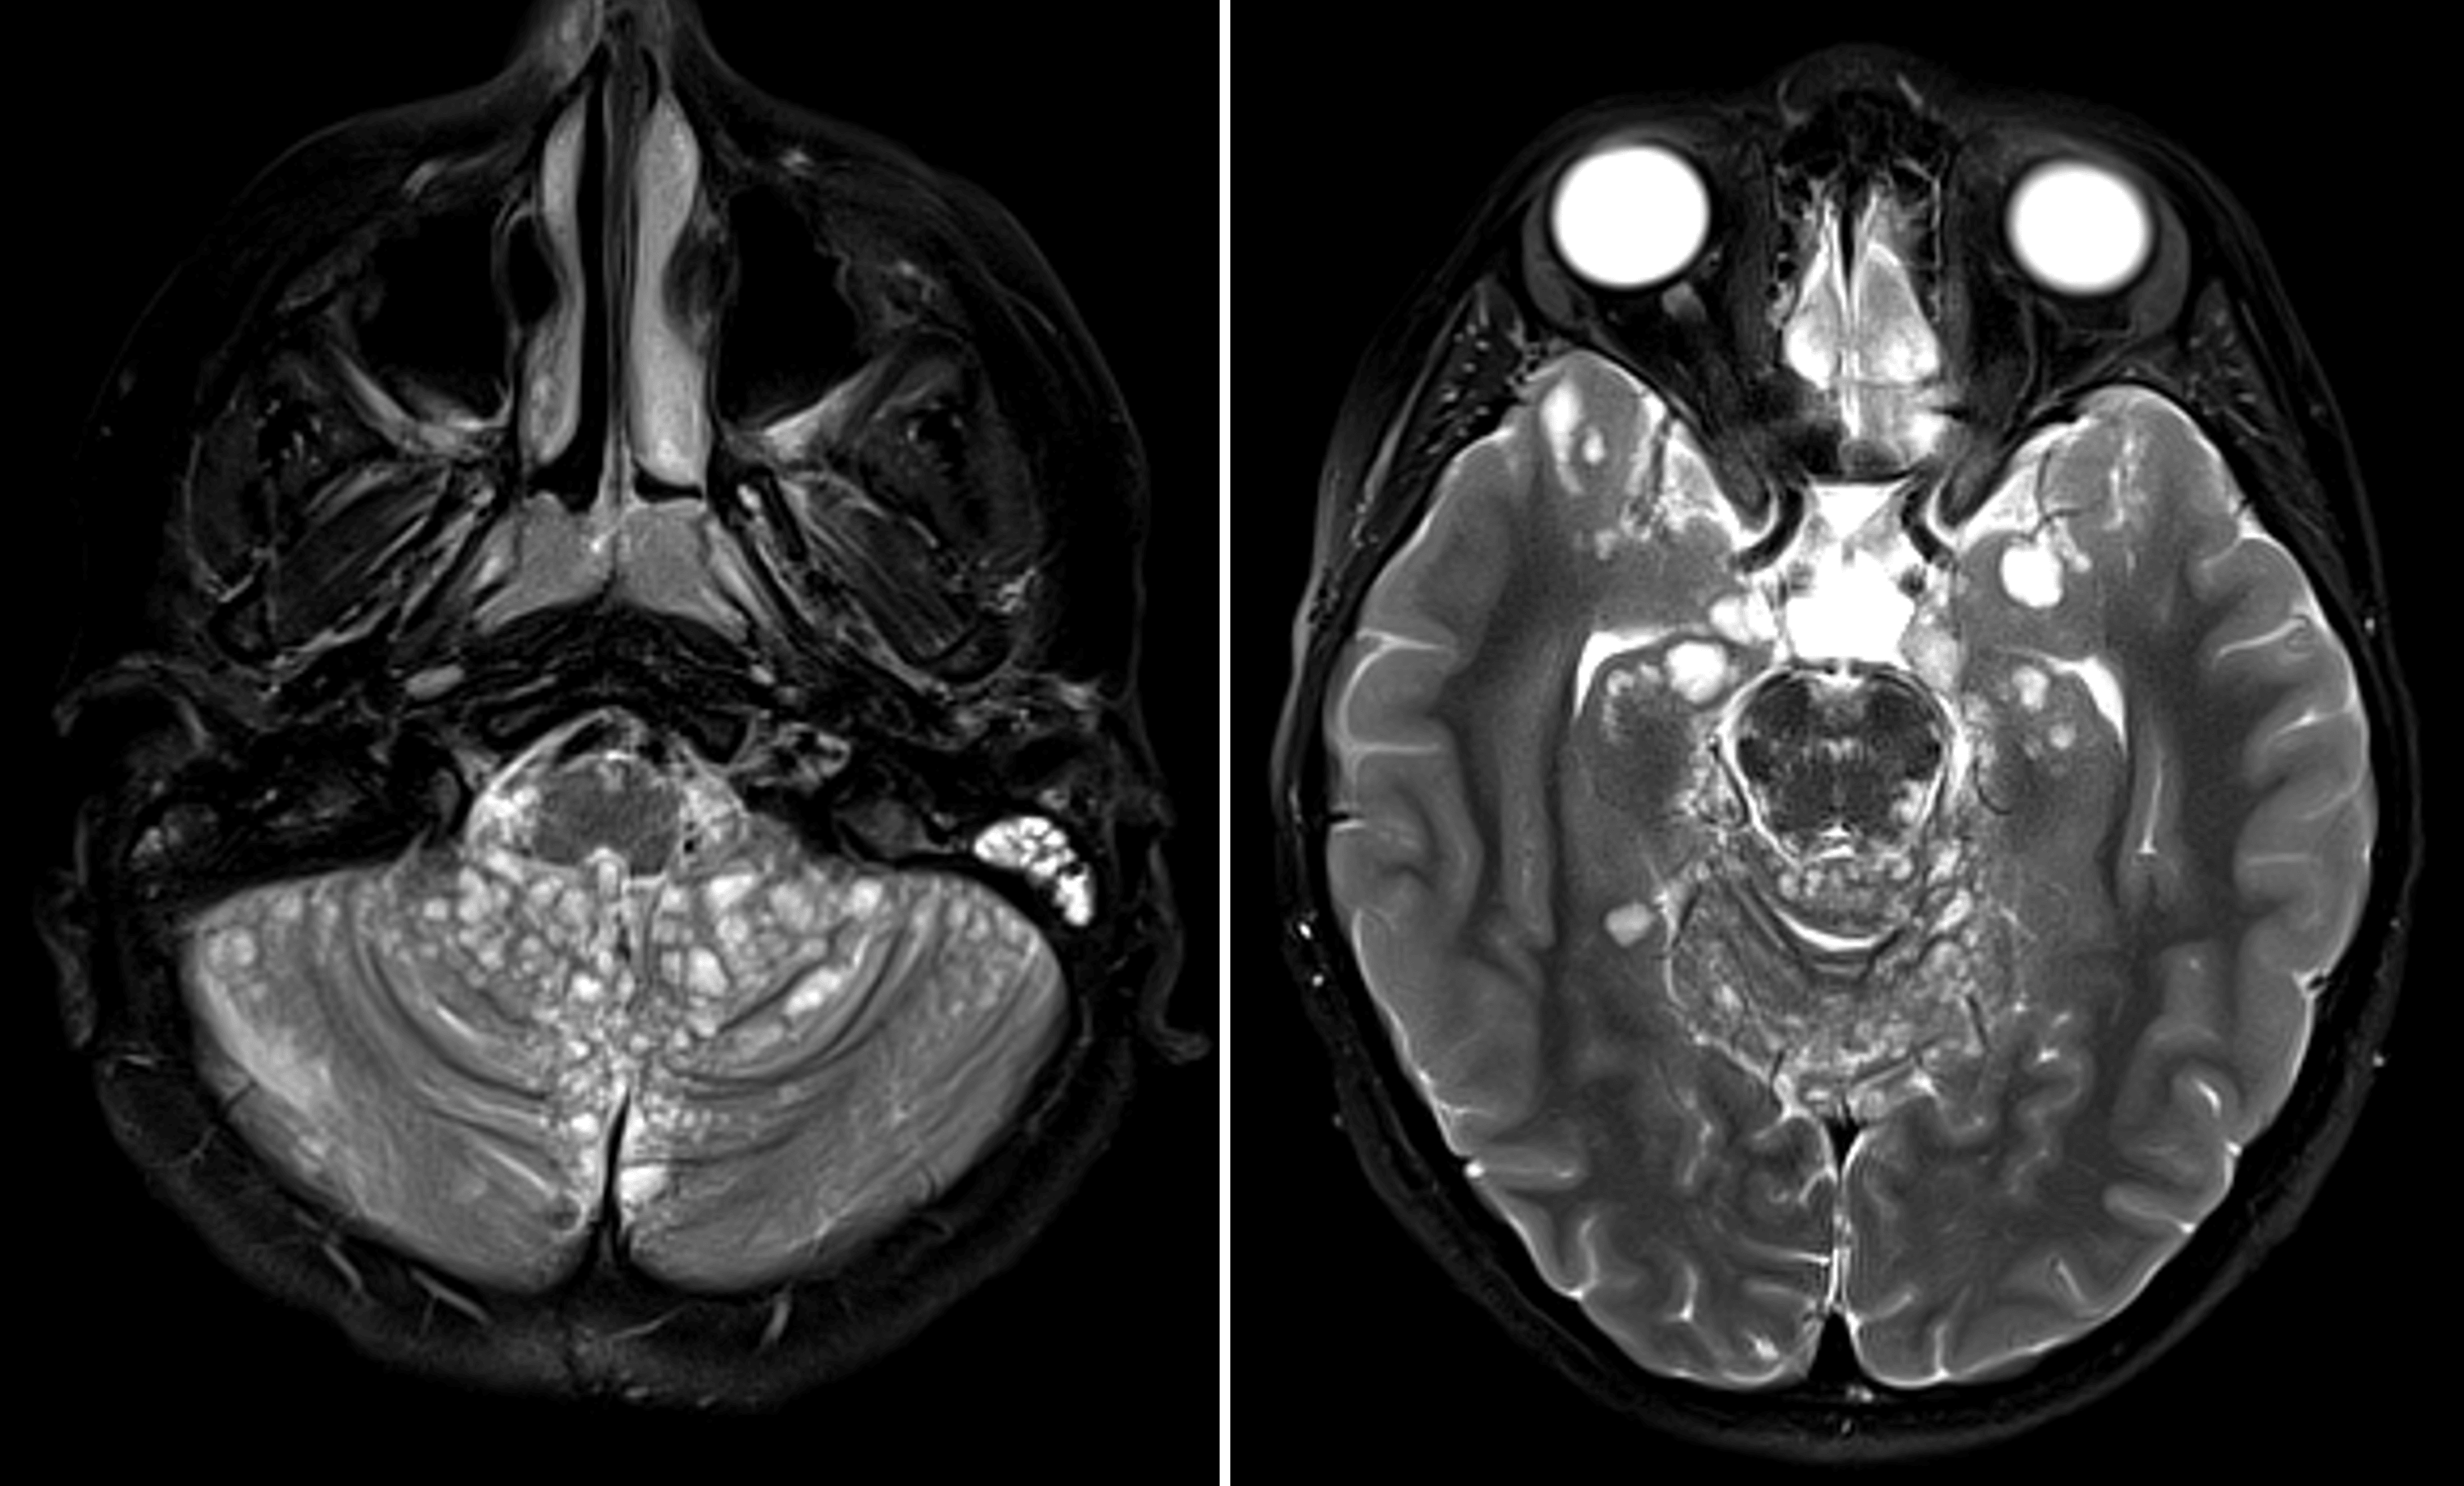

• Numerous T2/FLAIR hyperintense leptomeningeal lesions along the surface of the brainstem, cerebellum, hippocampi, thalami, basal ganglia, and inferior right frontal lobe

Numerous subpial cysts coating the brainstem, cerebellum, and inferior aspects of the supratentorial structures, which is a characteristic imaging appearance for diffuse leptomeningeal glioneuronal tumor.

Diffuse leptomeningeal glioneuronal tumor